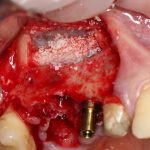

Я зафиксировал костный блок практически без адаптации на несколько винтов. Обрати внимание, что винты находятся в зоне, где не планируется установка имплантатов. Фиксация должна быть надежной, поскольку мне еще предстояла подготовка лунок для имплантатов. Трех винтов для этого вполне достаточно.

Дальнейшая адаптация костного блока свелась к сглаживанию острых краев. После чего я приступил к подготовке лунок и установке имплантатов.

Напомню, что для этой работы я выбрал субкрестальные имплантаты Ankylos C/X. Они прекрасно сочетаются с любым методом остеопластики.

Я не планирую установку супраструктур или коронок, поэтому на уровень первичной стабильности можно положить болт. Даже наоборот — чем меньше крутящий момент при установке, тем лучше. Для имплантатов Ankylos и подобных им, это особенно важно. В общем, момент силы при установке — не более 10-15 Нсм.

Ремарка: имплантаты с предустановленными имплантодержателями хороши тем, что с ними легко контролировать позиционирование имплантатов. В случае с Ankylos С/Х - еще и крутящий момент. Имплантодержатель должен отсоединяться от имплантата с легким щелчком. Если его клинит, и тебе приходится прикладывать для этого усилия, то ты, однозначно, превысил момент силы во время установки имплантата. Следовательно, жди проблем.

Глянем на то, что получилось:

Осталось адаптировать костный блок (убрать острые края), проверить его фиксацию и, при необходимости, добавить винты. Десятисекундное дело.